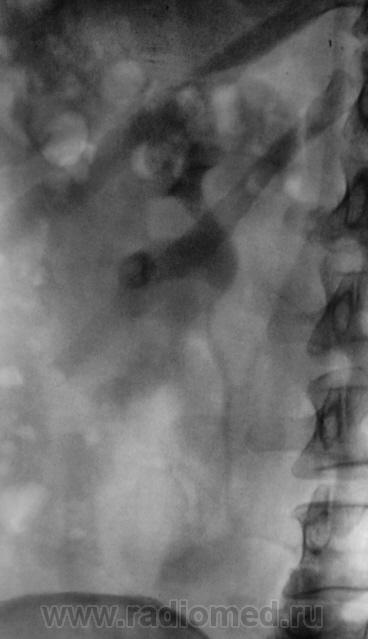

После введения контрастного вещества урограммы произведены на 7 и 15 минутах.

Да, контраст "покрыл" тень рентгеноположительного конкремента.

А мне этот конкремент, при всей его "рентгеноположительности", видится дефектом наполнения чашки, контрастированной ещё более "рентгеноположительным" контрастом)).

Ещё более отчетливо это может было бы увидеть на прицельной рентгенограмме почки либо томограмме её.